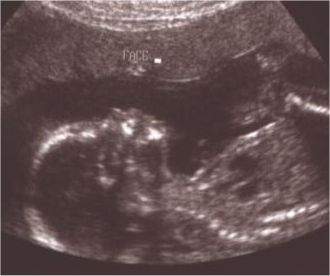

Her last Ultrasound on Jan.7, 2005

Added by Anonymous